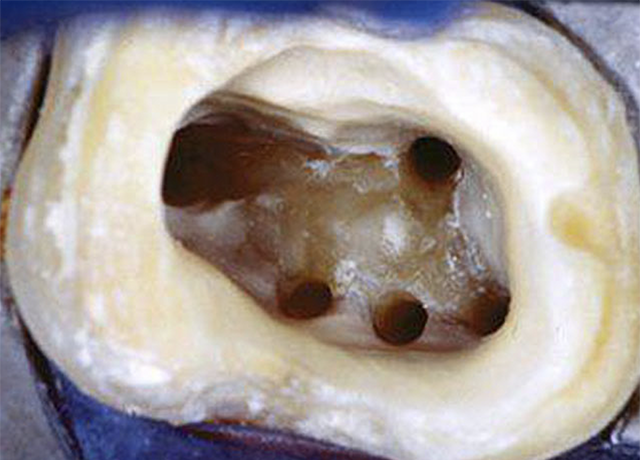

▲普通は3根管しかない歯なのに、マイクロスコープで見ると5根管ありました。5根管の穴をちゃんと見つけて消毒して、この後薬剤で根管充填しました。

▲根管口がこんなにはっきり見えます!